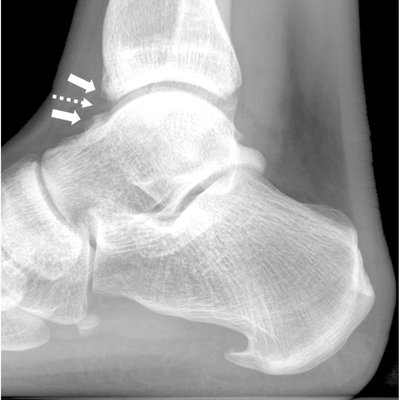

Click on an image below to view more info.